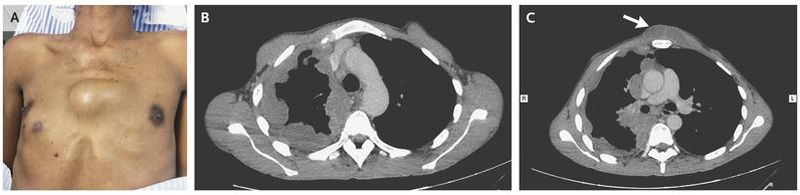

A 40-year-old man presented with a 3-month history of fever, weight loss, dyspnea, and cough. Physical examination revealed a tender, bulging anterior thoracic mass and a small ulcerative lesion that was inferomedial to the right nipple (Panel A). Computed tomographic scans showed a pleural effusion (Panel B) that extended through the chest wall (Panel C, arrow), along with accompanying bone destruction. Surgical exploration revealed purulent pleural fluid; a culture of the fluid grew Mycobacterium tuberculosis. Empyema necessitatis is a complication of pleural empyema that is characterized by extension of purulent fluid through the parietal pleura into the chest wall. A chest tube was placed for 3 weeks; the patient was treated for 9 months with rifampin, isoniazid, pyrazinamide, and ethambutol, and he recovered fully.